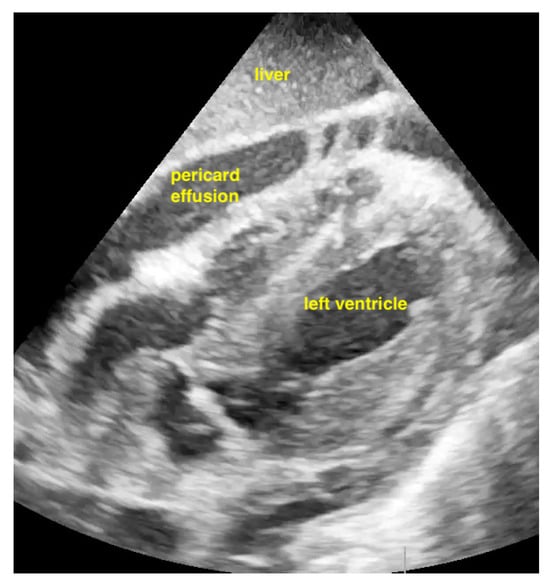

7.2.1. Pericardial Effusion

Pericardial effusions are best identified with a convex or sector probe in the subxiphoid or parasternal view. While it is important to simply note whether an effusion is present, sonographic and clinical (hypotension and tachycardia) evidence of cardiac tamponade should be sought. These include diastolic collapse of the right atrium free wall, followed by free wall collapse of the right ventricle as tamponade worsens. Both the apical and subcostal four-chamber views are ideal for this assessment. However, the subcostal window allows for a rapid transition to the proximal IVC view, which is dilated (>2 cm) and does not vary with respiration in cases of cardiac tamponade. Although many cases of medium and large pericardial effusions are obvious on ultrasound, there are notable exceptions. These include some hemorrhagic effusions which show significant coagulation, thus appearing echogenic on ultrasound, leading to frequent confusion with an epicardial fat pad or even a portion of the myocardial wall. Conversely, some epicardial fat pads may be confused with pericardial effusions, especially by novices. Differentiating between the two is easy by using anatomical knowledge. An epicardial fat pad does not extend enough inferiorly to be seen on a longitudinal IVC inlet view, while a pericardial effusion will in virtually all cases (Figure 7, Figure 8, Figure 9 and Figure 10).

Figure 7.

Pericardial effusion in parasternal long-axis view.

Figure 8.

Pericardial effusion in subxiphoidal view.